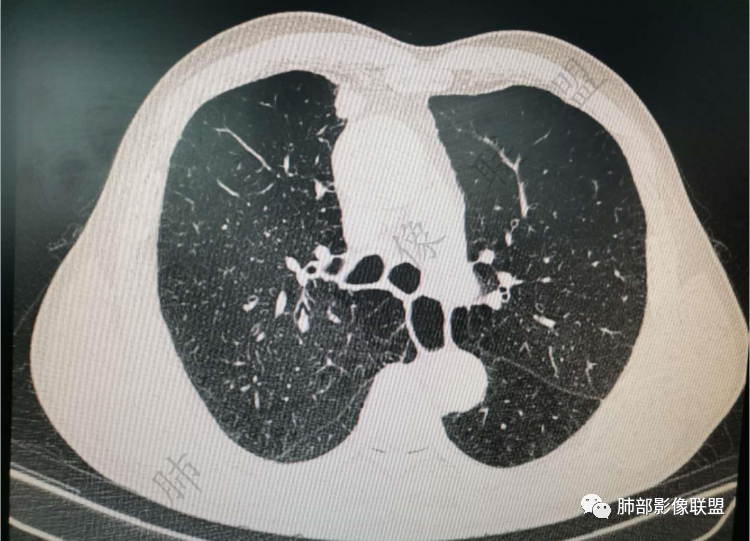

肺气肿背景

实性有隆起的小结节,内部有坏死、周围包括内乳动脉有增粗

老年男性,肺气肿背景,右肺上叶胸膜下弧立实性不规则结节,密度不均,其内低密度坏死影,支气管似有截断,血管集束,2月复查明显增大,考虑恶性,鳞癌可能大,鉴别炎性肉芽肿

老年男性,肺气肿背景,右肺上叶前段胸膜下结节,部分边缘毛糙,血管集束增粗,支气管似有截断,胸膜牵拉,结节密度不均,两个月随访结节有增大,考虑恶性,肺癌可能;另右肺上叶后段肋胸膜区小片状类结节影,考虑炎性可能。

右肺上叶前段结节,边缘毛糙,血管进入,局部细支气管似闭塞,增强有强化,中心密度似减低,2月明显增大,肺气肿背景,首先考虑炎性结节,鳞癌增大可以很快,对比老片看看

右肺上叶前段胸膜下结节,近段支气管截断,血管伸入结节内,密度不均,同侧临近内乳动脉增粗,不均匀强化,肺气肿背景,两月明显增大,考虑低分化鳞癌,隐球菌代排

老年男性,无症状,炎性指标增高。肺气肿背景,右肺上叶前段结节,边缘部分平直部分澎隆,血管集束,支气管至病变边缘似截断,近端扩张。增强环形强化,中心坏死。两月内病灶增长太快,考虑炎性肉芽肿,慢性脓肿?结核?癌待排。

支气管变形、壁增厚,提示慢性支气管炎症